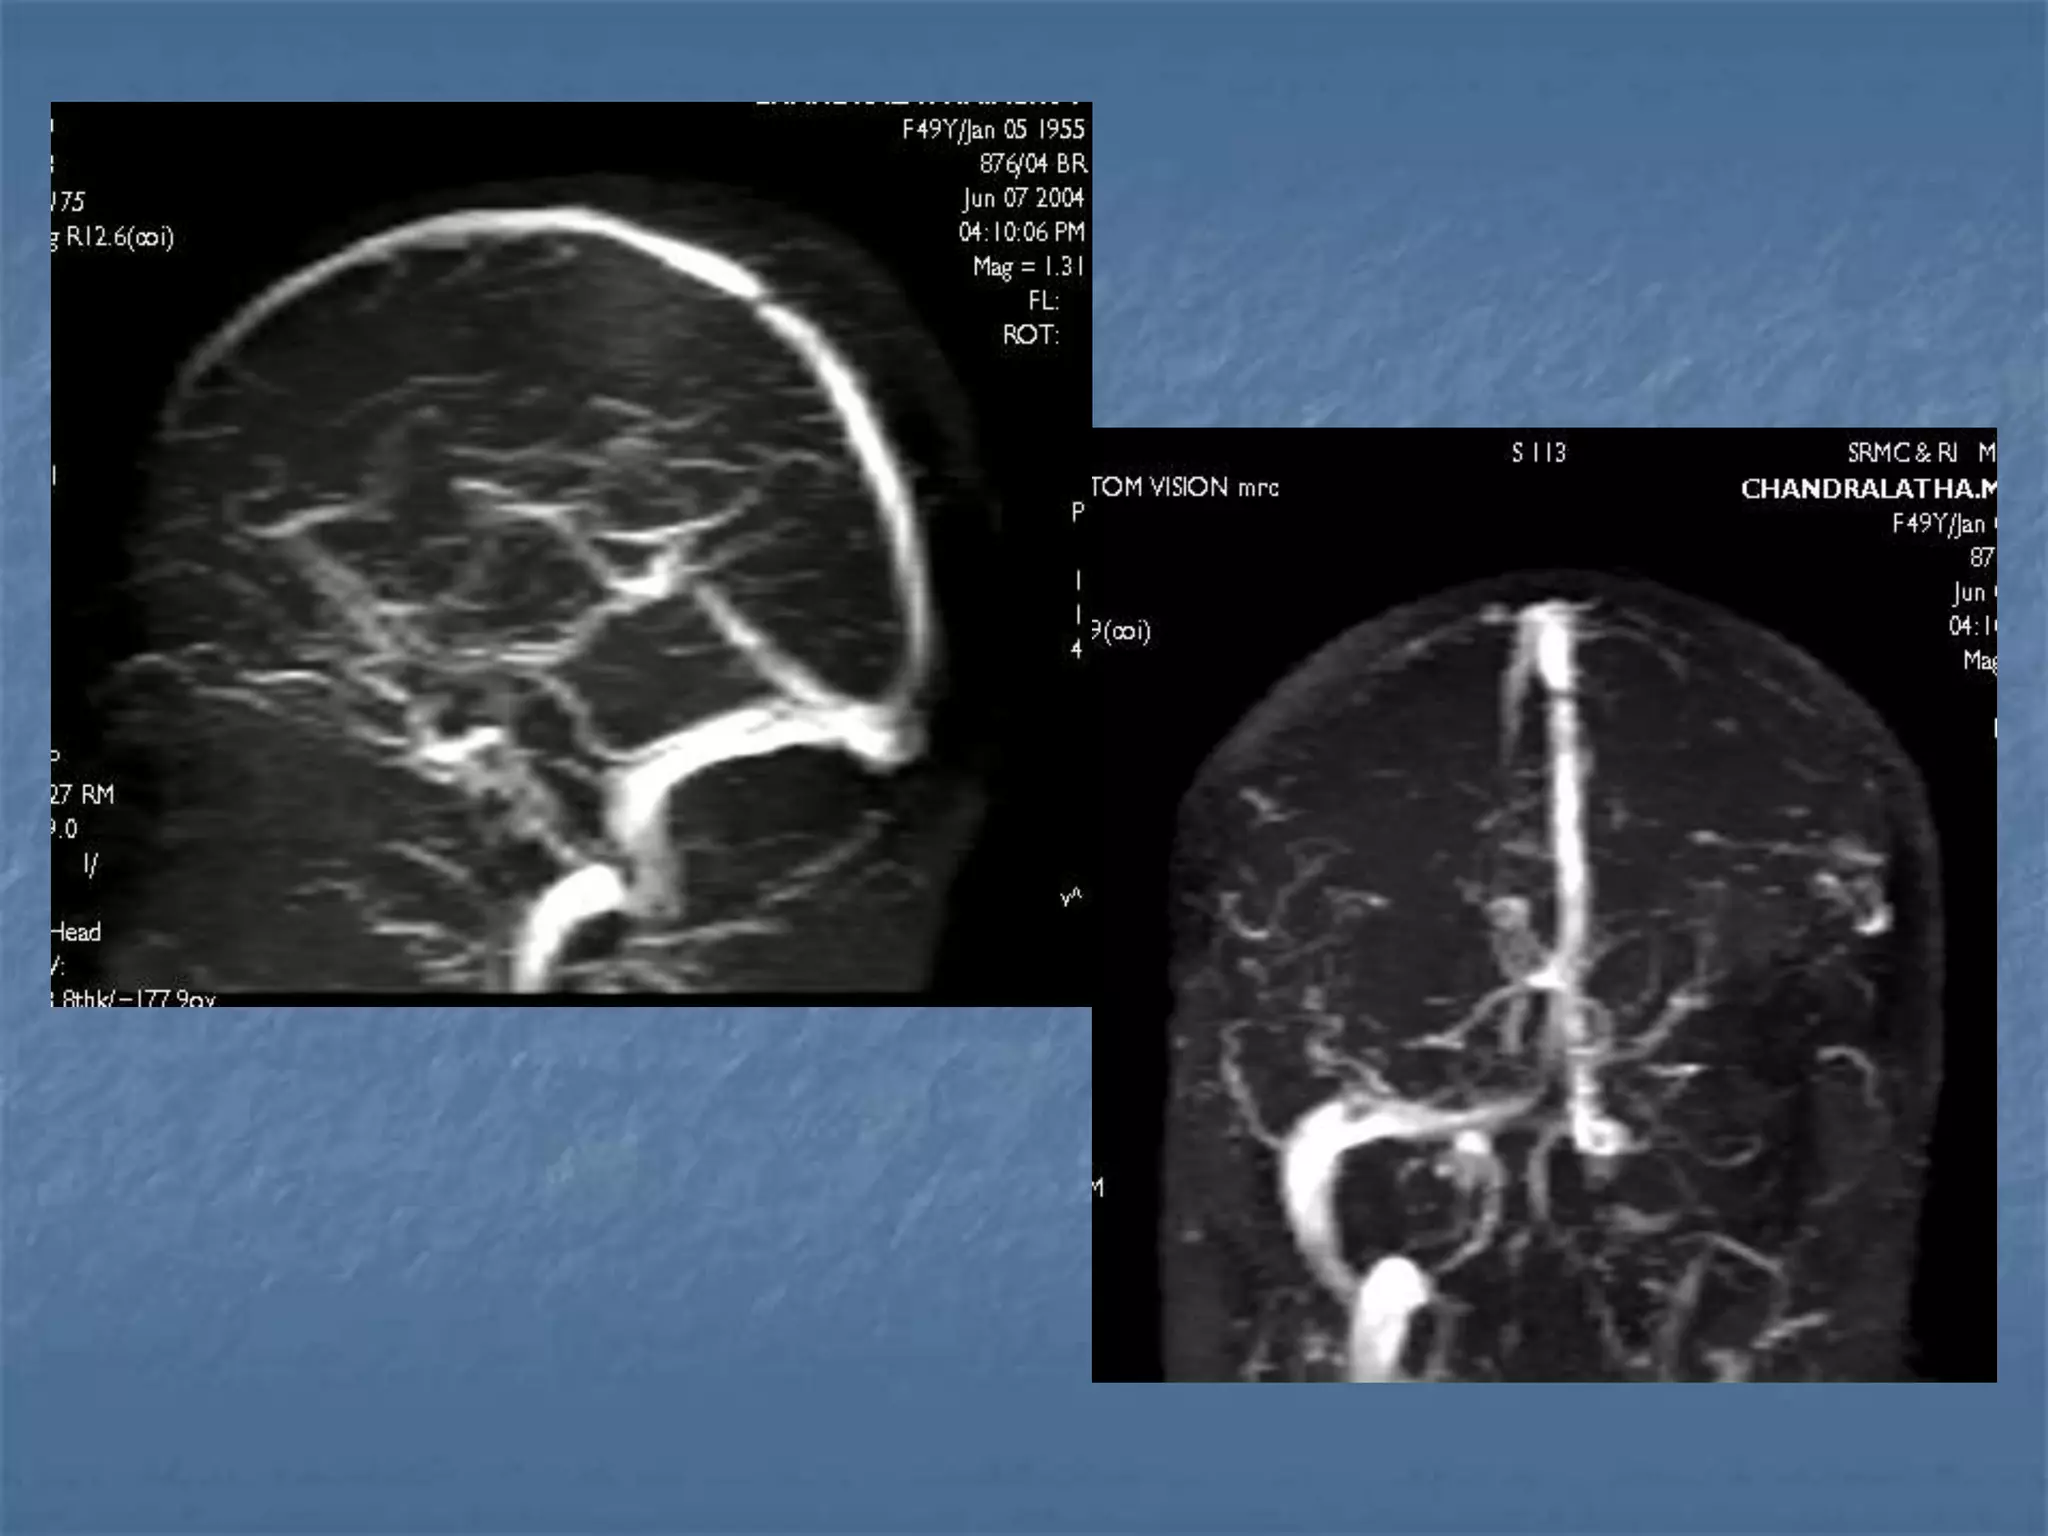

Venous Sinus Thrombosis with Venous

Infarct

 Clinical symptoms – head ache, seizures

 Pathology is due to decrease in perfusion pressure as

the venous pressures elevate due to occlusion.

 Predisposing conditions are dehydration, infection,

polycythemia, sickle cell disease, hypercoagulable

states, peripartum, OCP poisoning.

Imaging findings

 Unilateral / bilateral parenchymal hypodensities

 Not limited to an arterial territory

 May be associated with hemorrhage

 Signs: Delta sign, Enhancement of walls of sinus than

their contents.